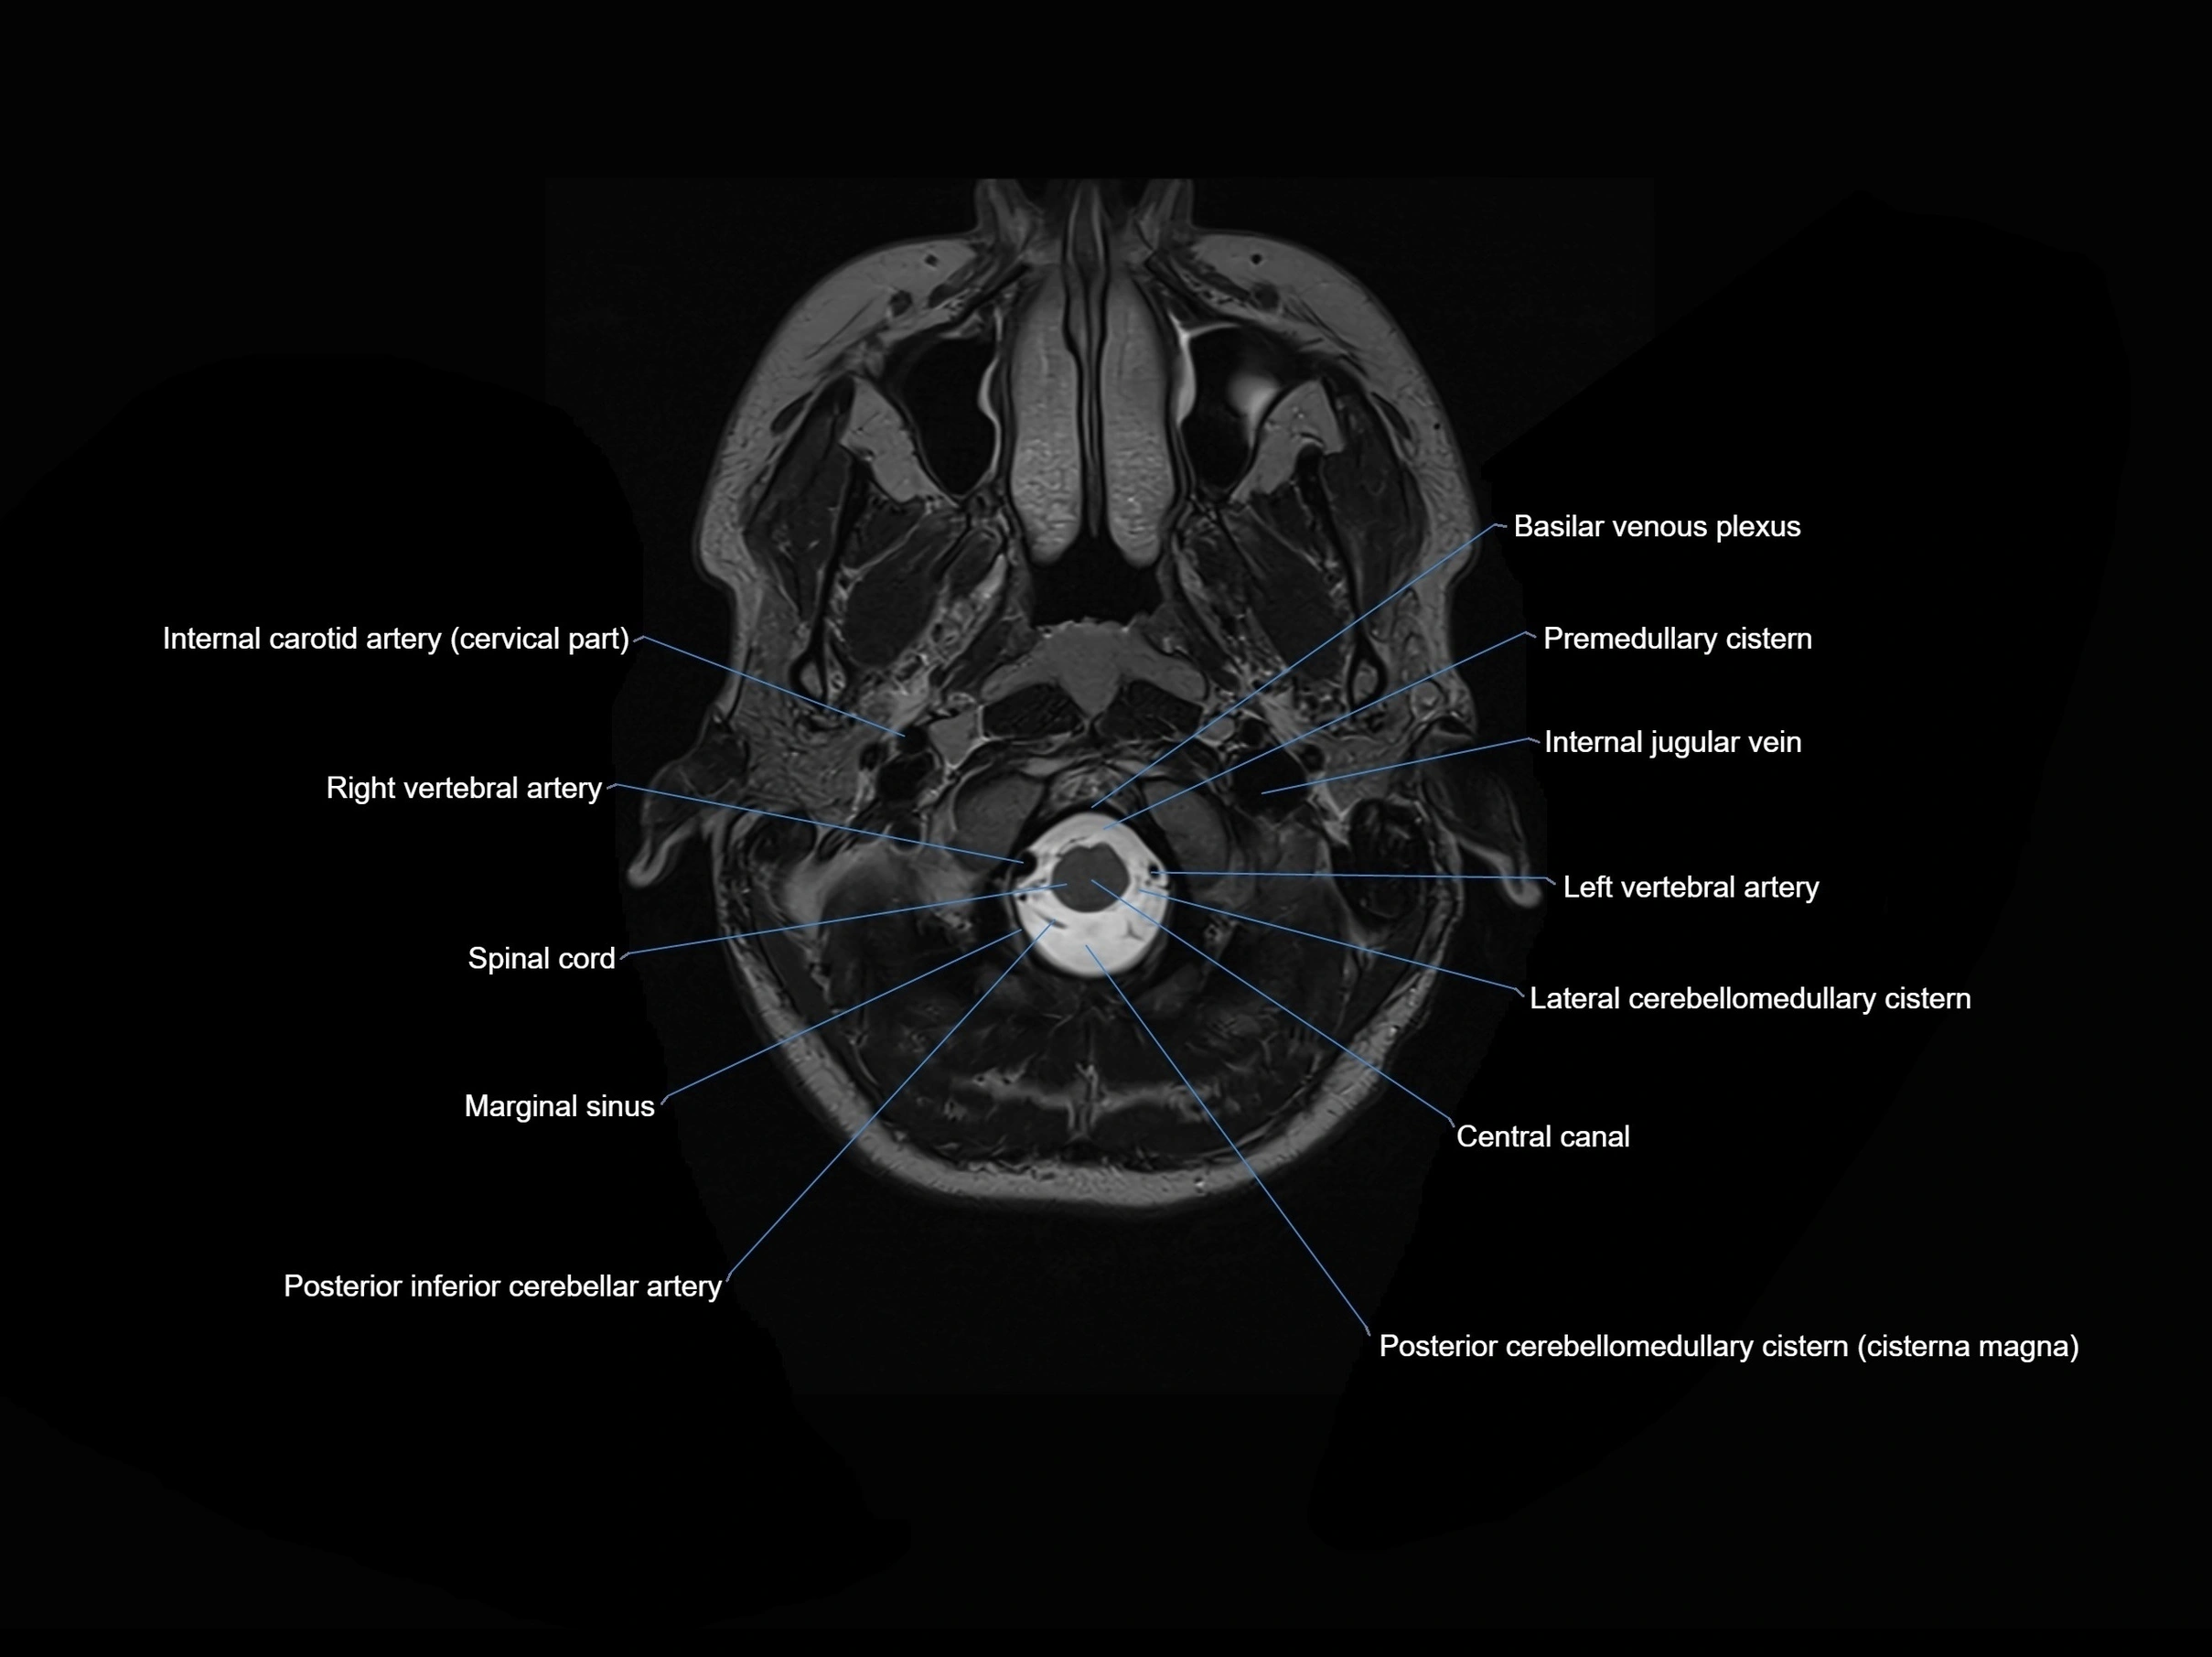

MRI images